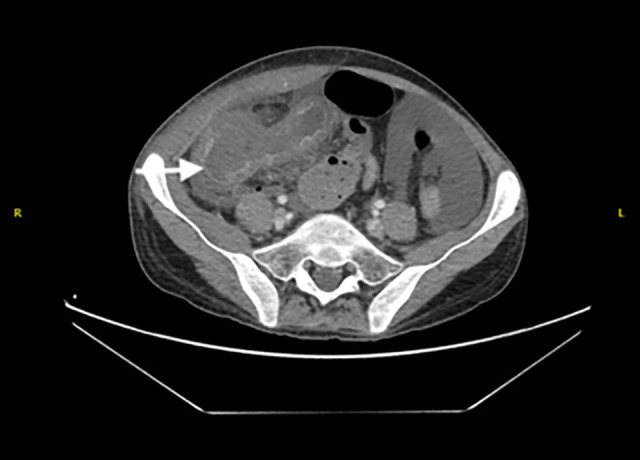

BACKGROUND Gastrointestinal mucormycosis is an underrecognized and underreported fungal infection with a high mortality rate. Diagnosis is often confounded by a non-specific constellation of signs and symptoms. We present a case of neutropenic colitis and ileocecal perforation secondary to gastrointestinal mucormycosis. CASE REPORT The patient was a 19-year-old man recently diagnosed with B-cell acute lymphoblastic leukemia, on active chemotherapy. He presented with abdominal pain and tenderness, and a contrast-enhanced CT revealed neutropenic colitis. Despite broad-spectrum antibiotics, his condition worsened, prompting reassessment. Follow-up CT showed bowel ischemia and a pelvic collection. He underwent an emergency laparotomy, which revealed destruction of the anterior cecal wall and detachment from the terminal ileum and ascending colon. Ileocecal resection was performed and histopathologic examination demonstrated angioinvasive fungal elements consistent with Mucor spp. He was diagnosed with gastrointestinal mucormycosis and promptly started on amphotericin intravenously. He improved over the next 2 weeks and was discharged with a plan to continue his 6-week course as an outpatient, followed by oral posaconazole maintenance therapy. Several weeks later, his infection relapsed secondary to non-compliance. He underwent repeat surgical debridement and antimicrobial therapy was restarted with intravenous amphotericin and Isavuconazole. He successfully completed 6 weeks of treatment and was transitioned to oral Isavuconazole prophylaxis. He remained stable and relapse-free at 6 months following his second procedure. CONCLUSIONS The case highlights the importance of early recognition of patients at risk for this infection, maintaining a high index of suspicion, and employing aggressive medical and surgical management strategies to avoid mortality.